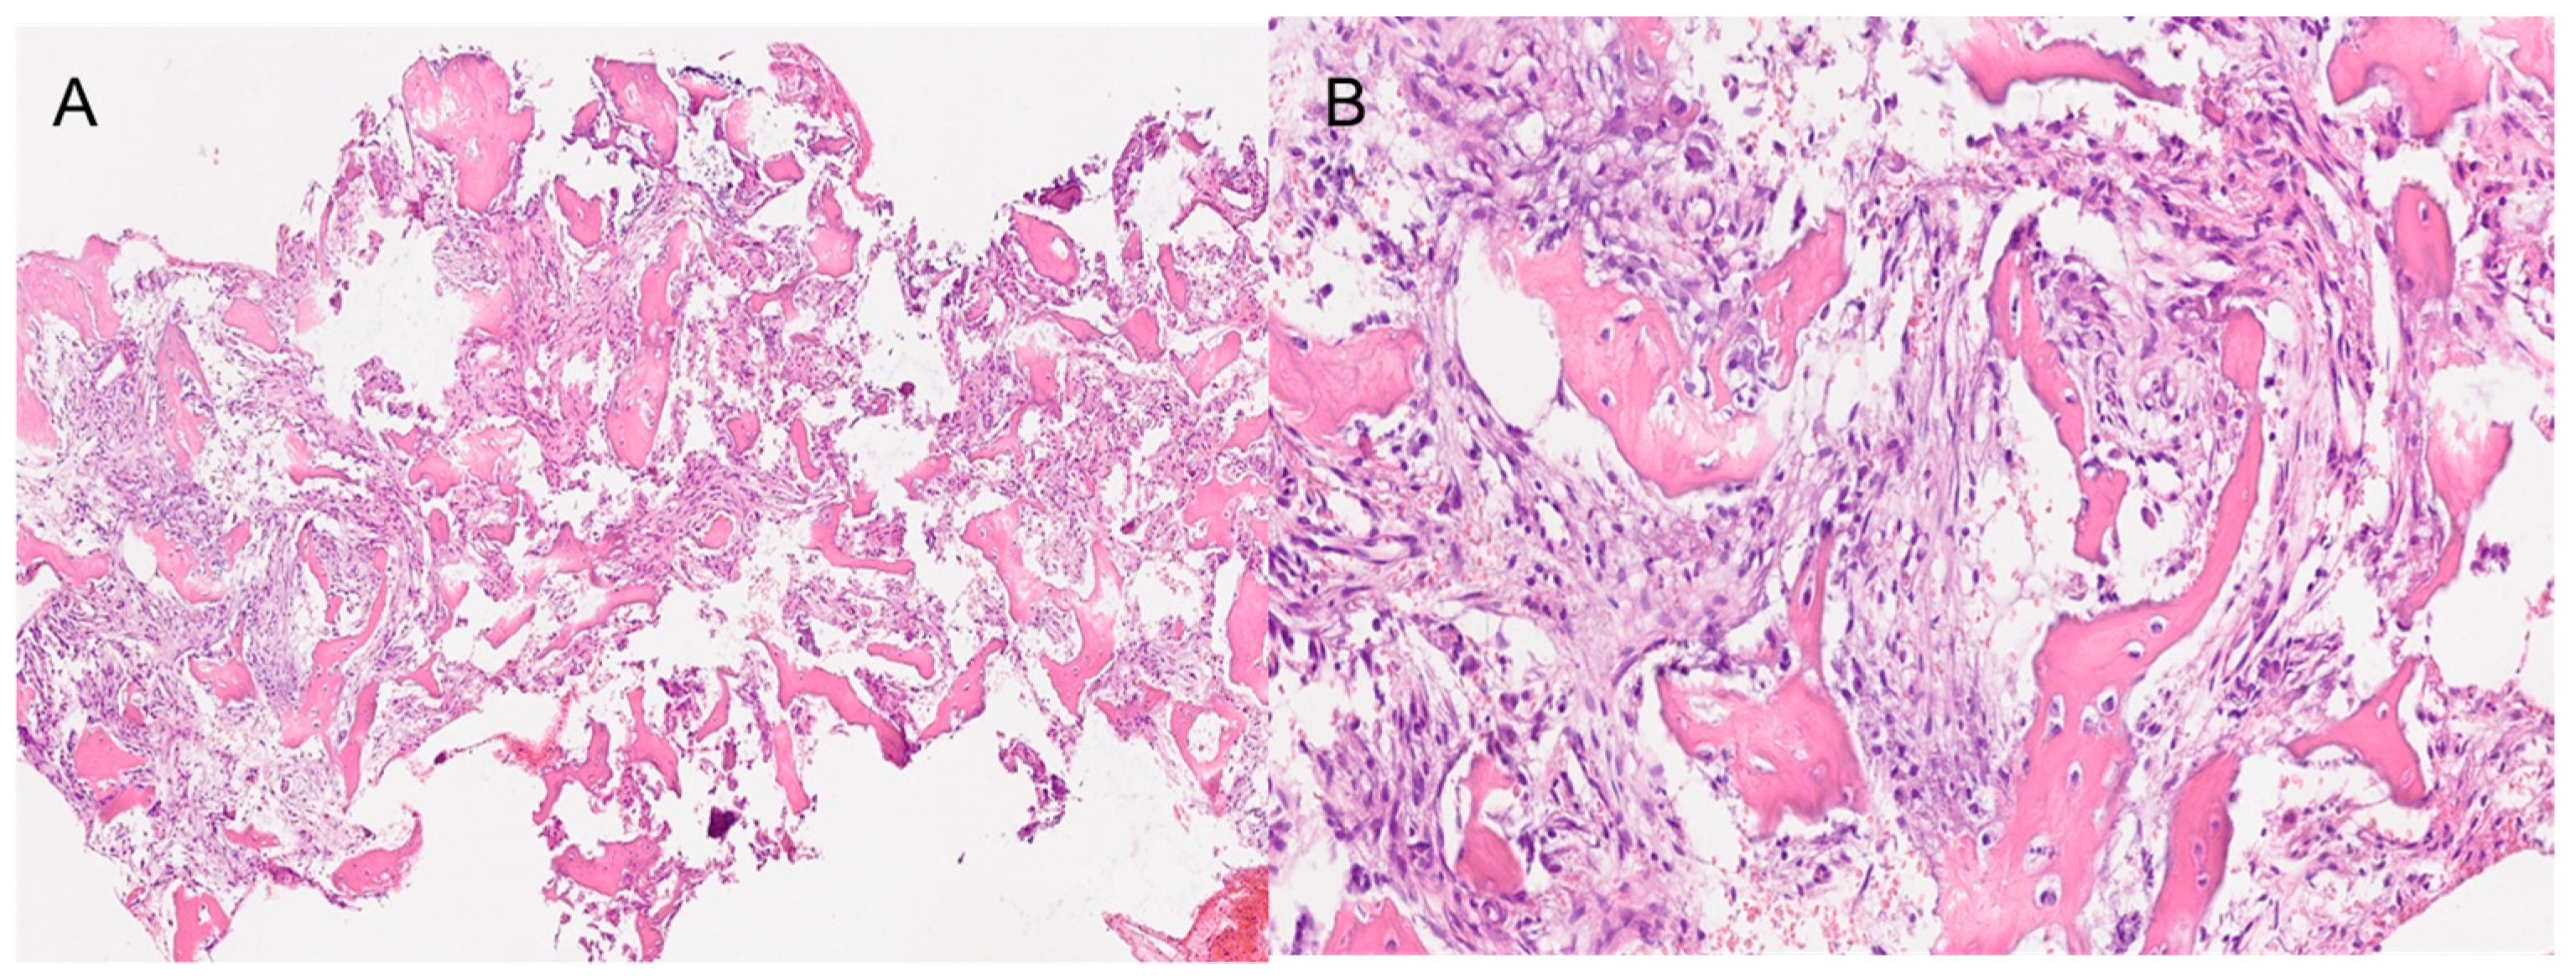

Both histological reports confirmed the diagnosis of fibrous dysplasia, showing a bone-fibrous fragment including bone trabeculae with irregular distribution with a crossed fibers structure with marked remodeling, and a non-atypic fibrous tissue with several vascular structures with thick and mineralized walls (Figure 3).

Figure 3.

The histopathological images show a section of the middle turbinate. (A) 4× magnification. (B) 20× magnification. Both images show the main characteristics of fibrous dysplasia, such as fibrous tissue intermixed with irregularly distributed bony trabeculae.

Moreover, in continuity with this tissue, they showed a de-epithelialized mucosa with normal gland structures. The Ki67 expression shown was <5%.